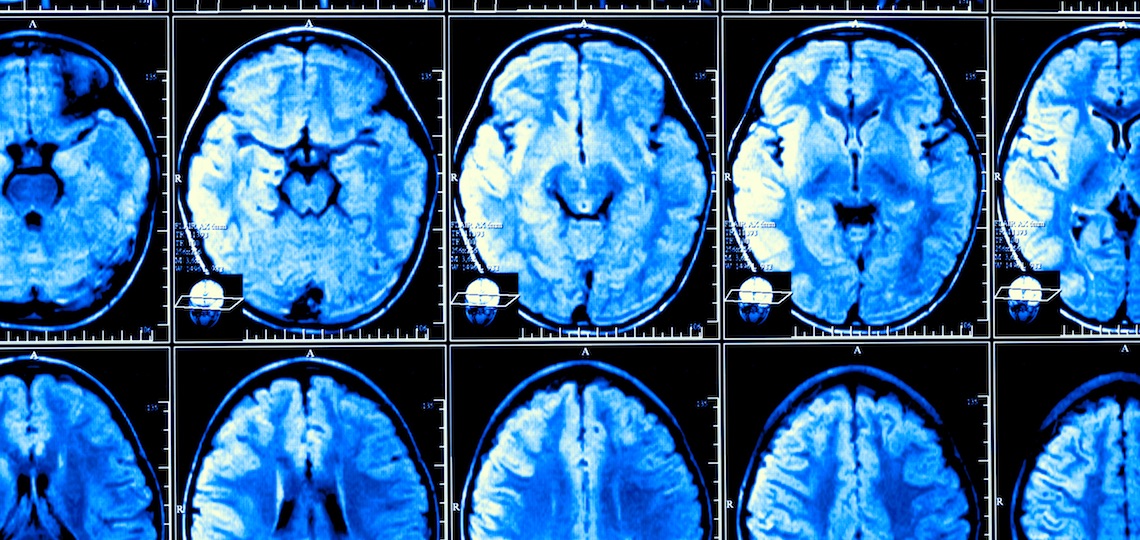

1999年至2019年期间,研究人员对3226名出生于1930年至1970年的人进行了脑部核磁共振成像检查,其中女性占53%,男性占47%。所有参与者都没有认知障碍或中风病史,而中风会增加痴呆症风险。

研究人员将 20 世纪 30 年代出生的人的核磁共振成像与 20 世纪 70 年代出生的人的核磁共振成像进行比较后发现,有几种大脑结构的大小在逐渐但持续地增加。其中,颅内容积(ICV)或颅骨(头盖骨)内的容积逐年增加,从 30 年代的平均 1,234 毫升/41.7 盎司增加到 70 年代的 1,321 毫升/44.7 盎司–增加了 6.6%。

白质和皮质灰质的大小也有所增加。灰质是大脑(皮层)的最外层,对精神功能、记忆、情绪和运动都很重要。中风、帕金森病和阿尔茨海默病等多种疾病都会影响灰质。白质位于灰质之下,包含数百万束神经纤维(白质之所以呈白色,是因为髓鞘包裹着神经纤维)。从 20 世纪 30 年代到 70 年代,研究人员观察到白质的体积增加了 7.7%,皮质灰质的体积增加了 2.2%。海马体的体积也增加了 5.7%,海马体的最大作用是保存短期记忆并将其转移到长期储存中。皮质表面积,也就是看起来皱巴巴的可见灰质层,增加了 14.9%。